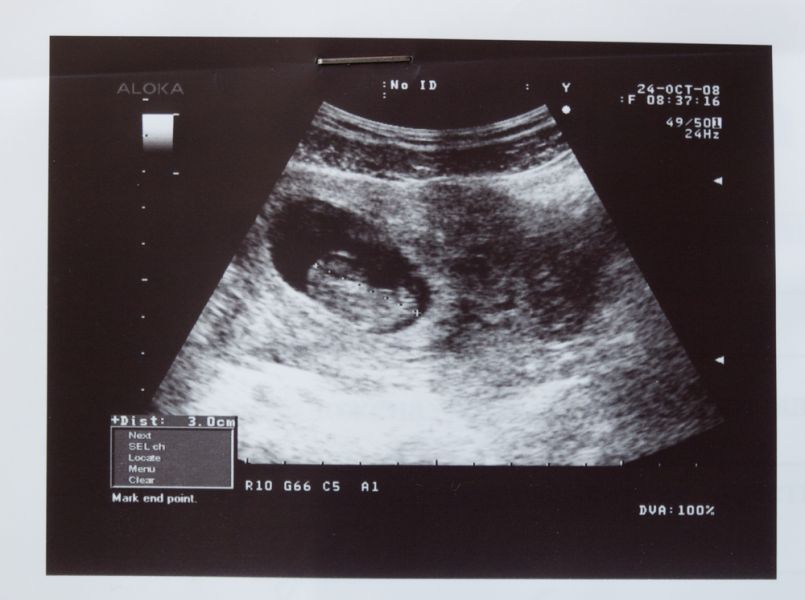

Vorige week schreven we al over het plan van Minister Schippers. Ze vindt dat vrouwen die ongewenst zwanger zijn in de eerste weken ook bij de huisarts terecht moeten kunnen om de zwangerschap af te breken. Dat kan met een pil. Maar volgens het Nederlands Genootschap van Abortusartsen (NGvA) ''moet niet lichtvaardig aan de abortuswet getornd worden''.